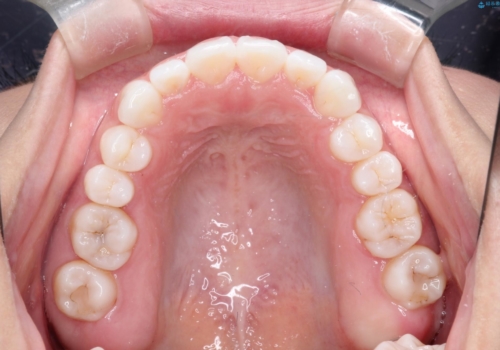

- 初診時には前歯部に捻転や叢生、臼歯部にも一部叢生が見られる状態でした。

インビザラインでの治療を計画し、行っていきました。

インビザライン治療により、捻転を含む歯列もしっかりと改善しています。

基本的な不正咬合部分は初回の30枚のマウスピースでほぼ改善しており、リファインメントでは前歯部の細かな調整など、患者様の要望を取り入れる形でシミュレーションをセットアップし、満足の行く結果に仕上がりました。